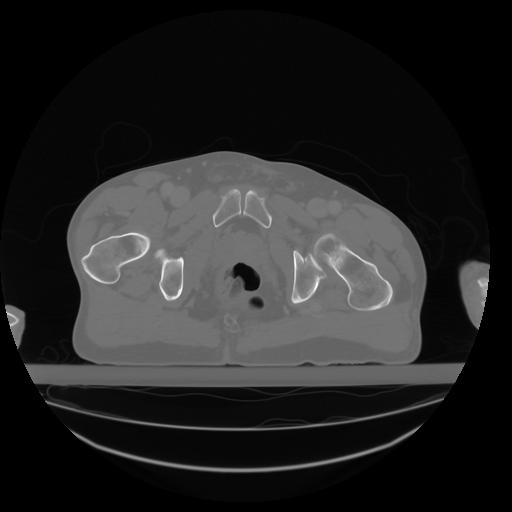

27 CUERPO,CE,Axial,3.0,CUERPO,,